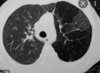

Patrón de atelectasia

Colapso del tejido pulmonar con pérdida de volumen

33

Causas de atelectasia

+ Obstrucción + Compresión

34

Clave para diagnóstico de atelectasia

Buscar tráquea